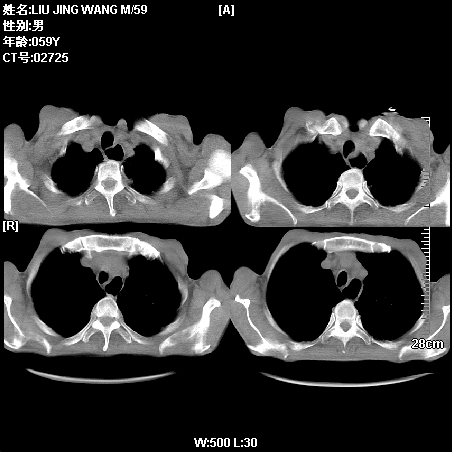

肿瘤科住院病人,都有食管癌史,都有放化疗治疗,两下肺病变是转移灶?还是其他原因造成?请老师指点

病例一 现呼吸困难,经抢救多次,咳嗽咳痰,发现食管癌2个多月